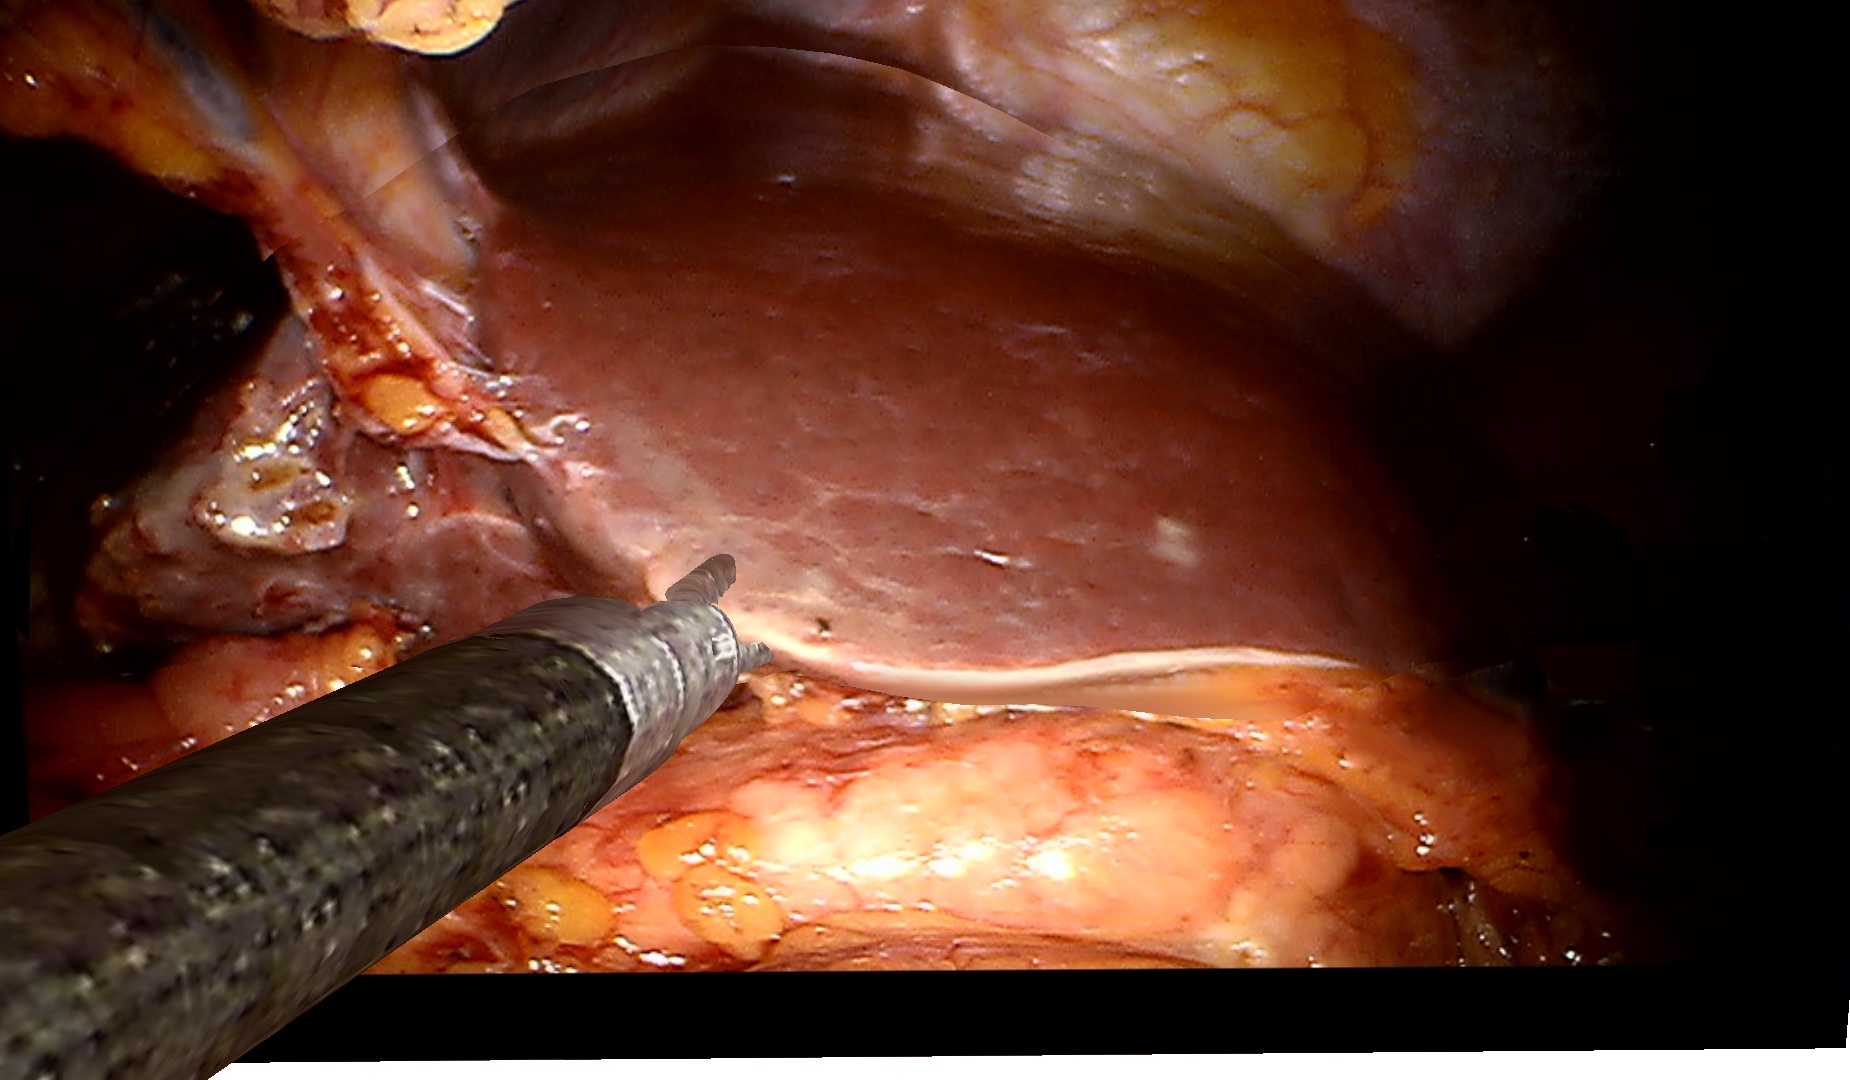

To demonstrate the effectiveness of our method on clinical data, we use a dataset of two visceral pig surgeries with a preoperative post-insufflation CT, initial rigid registration, a tracked laparoscope, and corresponding 2D monocular RGB videos. Surgical tools were masked out using SurgicalSAM [23]. The first sequence from the first surgery shows a tool-tissue interaction, whereas the second one shows a breathing motion without external manipulation. Because there is no deformed ground truth, as measuring intraoperative deformation would require intraoperative scanning, we demonstrate qualitative results.

Figure˜4 shows results on the tool-tissue interaction. The surgical tool presses down on the stomach, leading to the deformations tracked in the deformed mesh and CT (bottom rows). Although the difference in pressure applied between B and C appears marginal, we successfully track the increasing deformation, the difference being visible in both mesh and CT. For D and E, the tool is repositioned, now pulling the stomach back. Note how this backward pull is visible in the respective deformed CTs by a deformation to the right, since the laparoscope captures the scene roughly in the coronal plane, whereas the CT slice is shown in the sagittal plane.

Refer to caption

Figure 4: Examples from a tool-tissue interaction sequence. Rows from top to bottom: input images acquired by the laparoscope, images rendered with our method, deforming mesh, and deforming CT. Arrows in A point to the deforming anatomical structure, circles in B highlight the area of deformation, and arrows in E visualize the pull direction. See video in the supplementary material.

Since we rely on an initial registration, we are also subject to registration errors. There is a slight misalignment between the structure being manipulated in the input images (stomach) and the deforming mesh. Also note that we initialize our mesh from a post-insufflation CT, ensuring that the initial mesh and the intraoperative state early in surgery are still very similar. Regarding the deformation of the CT, we can only capture surface deformations by deforming our mesh. A more realistic deformation of deeper layers would require biomechanical modeling. Apart from those caveats, the method does not work in real time yet. Given the strides being made in the 3D computer vision community around 4DGS, we are confident that this problem will be solved soon. Despite those limitations, the deformations of the stomach in the CT are sensible and correspond to the tool-tissue interaction as confirmed by a board-certified surgeon.